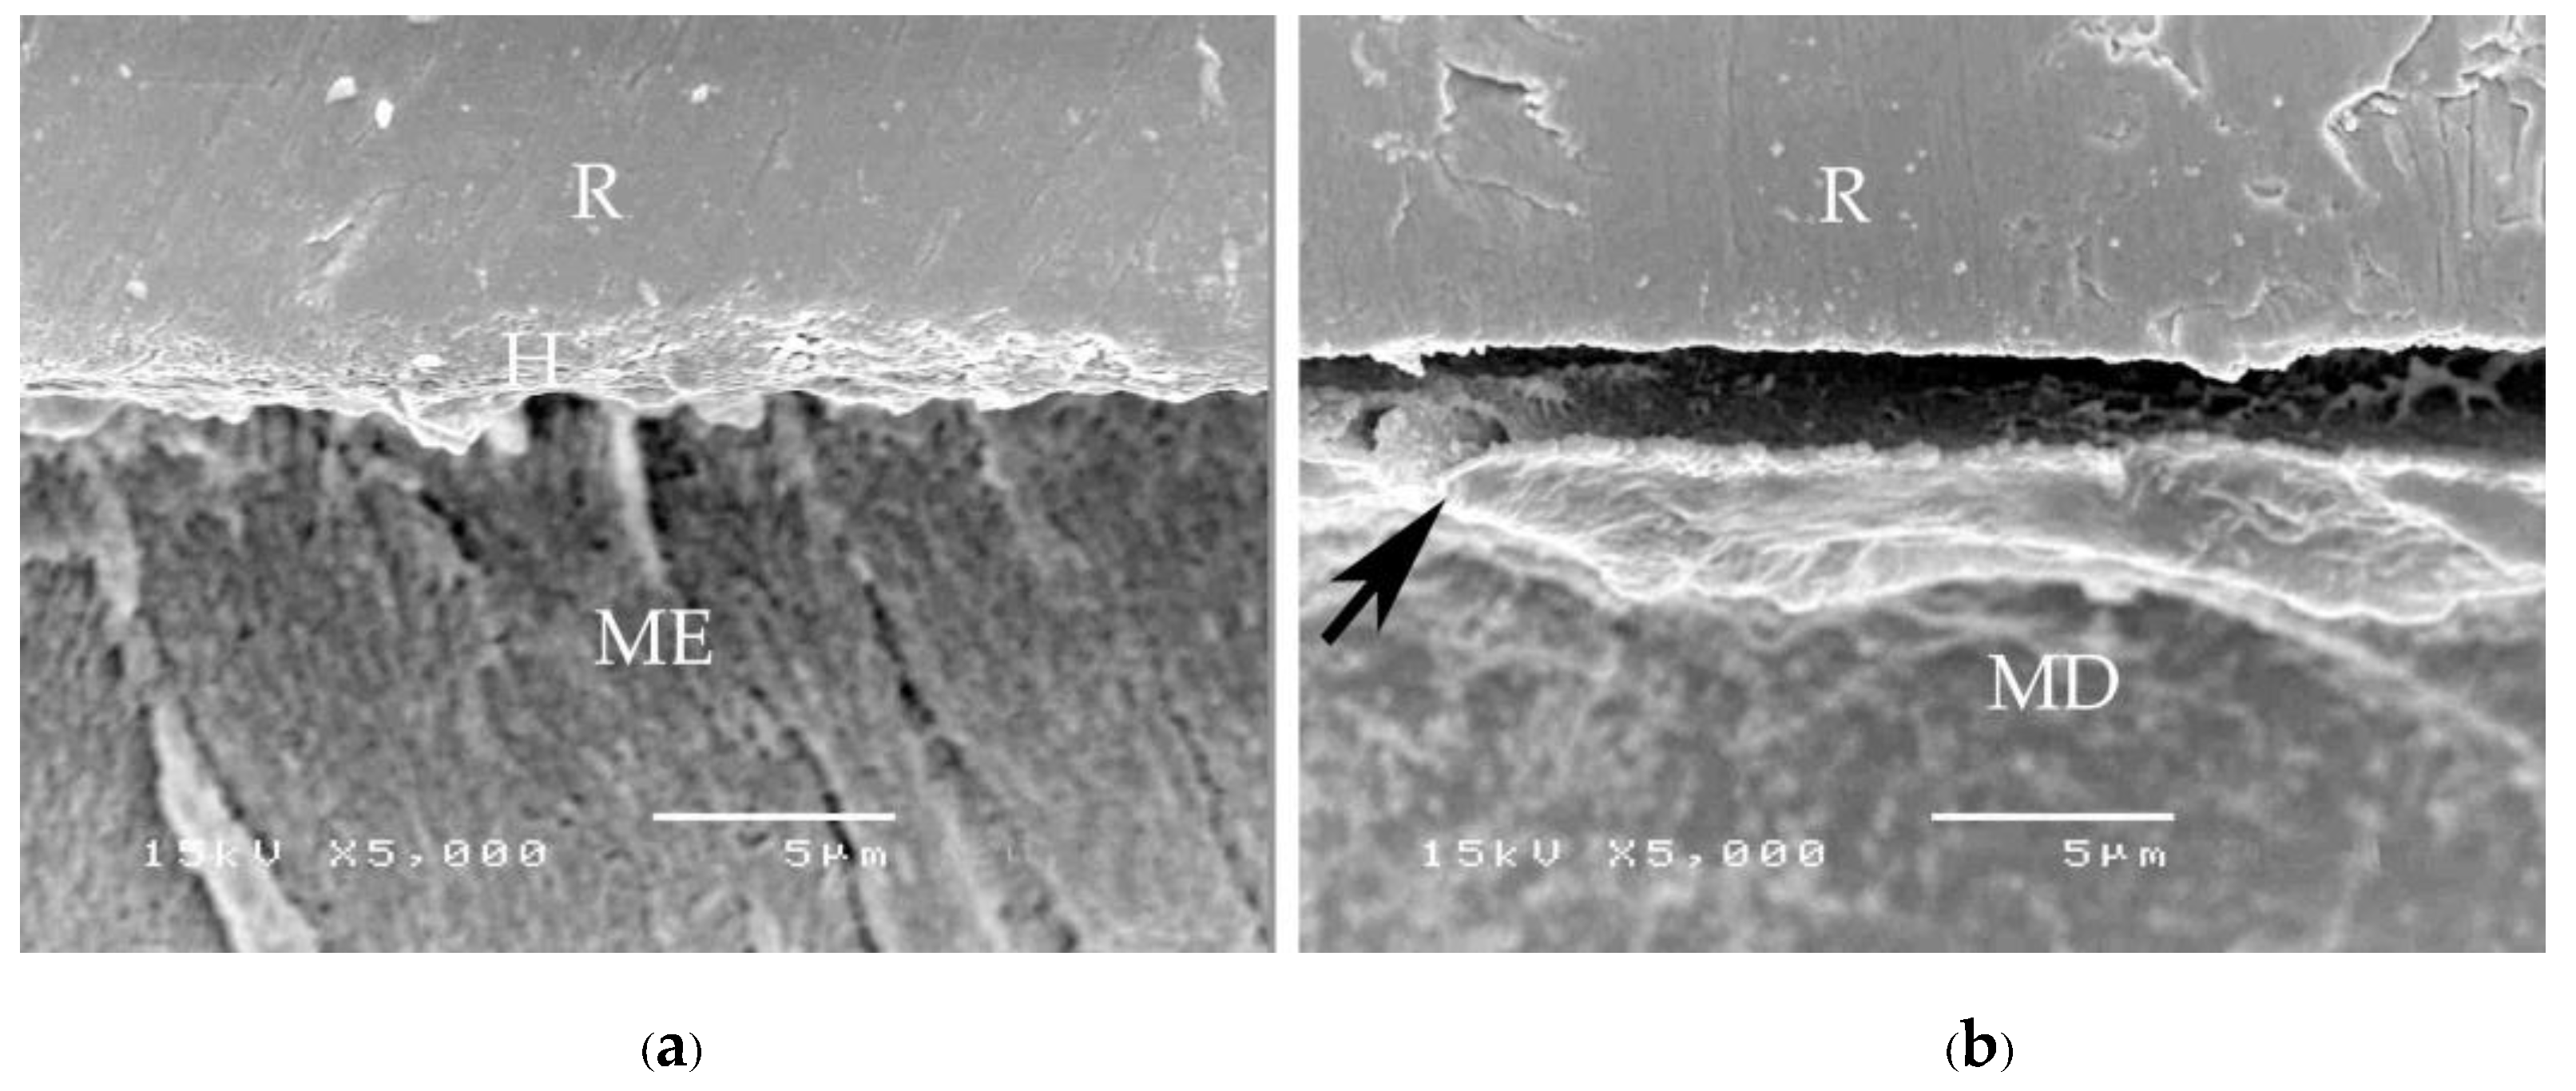

A consistent thickness of hybridized enamel or hybridized dentin after loading and the chemical challenge was found in primerless-wet (Figure 7) and dry bonding (Super-Bond C&B) (Figure 8) systems. A detached or degraded enamel- or dentin-resin interfacial layer was found in moist with primer (All-Bond2 and Single-Bond2) (Figure 9) and self-etch (AQ-Bond) (Figure 10) systems. The correlation between the dye penetration distance and the tensile bond strength data for the enamel and dentin-bonded interface was very weak (Pearson correlation = −0.148)

The mode of failure originating on the enamel surface suggests that resin infiltration into acid-etched enamel-DEJ-dentin using primerless-wet bonding and dry bonding using Super-Bond C&B could provide a tensile bond strength higher than that of the tensile strength of enamel itself (Figure 5). The complete hybridization of resin into the total etched enamel-DEJ-dentin depends on the demineralized tooth substrate’s permeability and the monomers’ diffusion potential. Non-detachment with consistent thickness hybridized layers against loading force for failure and chemical challenge found in the primeless-wet and Super-Bond groups (Figure 7 and Figure 8) suggest the high resin content encapsulates the tooth component in the hybrid layer. Therefore, the enamel- and dentin-resin hybrid layer, created using a primerless-wet bonding with 10 s to 60 s 1-1 conditioning, 4-META/MMA-TBB, and PMMA powder could be a sustainable biopolymer to provide a complete micro-seal and high tensile bond strength comparable with that of Super-Bond C&B. The long-range conditioning period of 1-1 for 10 s to 60 s ensures more safety manipulation in the clinical situation.

Figure 7. SEM micrographs of fractured specimens after chemical challenge demonstrating: the stable hybridized enamel (a) and hybridized dentin (b) of 1-1-30s primerless-wet specimens (H = hybrid layer, R = resin, ME = modified enamel, MD = modified dentin).